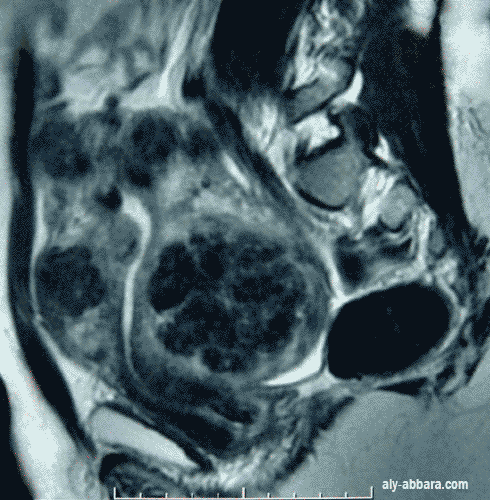

IRM (Imagerie par résonance magnétique)

Coupe sagittale médiane de la moitié inférieure de la cavité abdominale

Utérus polymyomateux occupant la totalité du petit pelvis et dépassant l'ombilic de quelques cm

(il a la taille d'un utérus gravide de 26 à 28 semaines d'aménorrhée)

Il est à l'origine de douleurs abdomino-pelviennes et de métrorragie

L'IRM a permis de mettre en évidence les structures utérines restant, la taille et la localisation des multiple fibromes